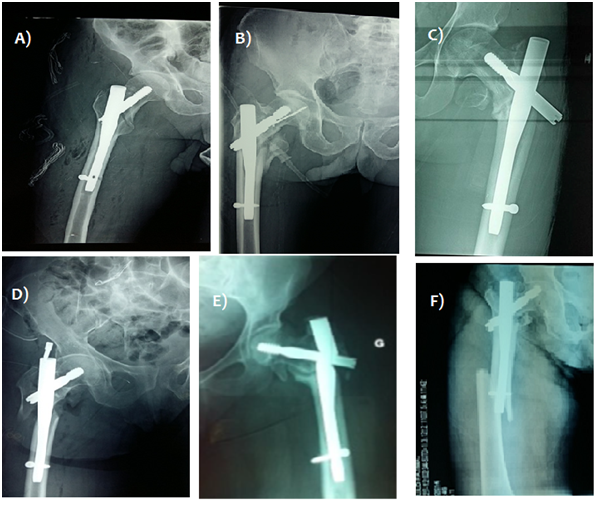

Patients’ folders were reviewed for intraoperative and postoperative complications and how they affected functional outcome. We uncovered 14 intraoperative complications (Figure 2) including 10 failed distal locking: posteriorly placed screws in all cases due to loosening of aiming device yet average parker score was 5 among this group of patients. A single (01) case of cervical guide pin breakage in the femoral head and 3 cases of pelvic penetration of the guide pin led to postoperative peritonitis in one patient and two fatal cases of abdominal hemorrhage that could not be managed intraoperatively.

Figure 2 A) Distal locking failure. B) Breakage of the guide pin in the head. C) Displacement of the cervical screw. D) Failure of lag screw blockage. E) Non-union with gamma implant breakage. F) Proximal diaphyseal femur fracture on one-month postoperative x-ray.

Postoperative complications were observed in 40 patients (8.8%) mainly diaphyseal femoral fractures and cervical screw cut out (Figure 2). 9 cases (2.2%) of proximal third diaphyseal fractures occurred between the 1st and 5th postoperative months with fracture line slightly distal to locking screw or tip of nail. All cases underwent nail removal and revision using long gamma nails in 6 cases and a femur nail in 3 cases with favorable outcome (Figure 3).